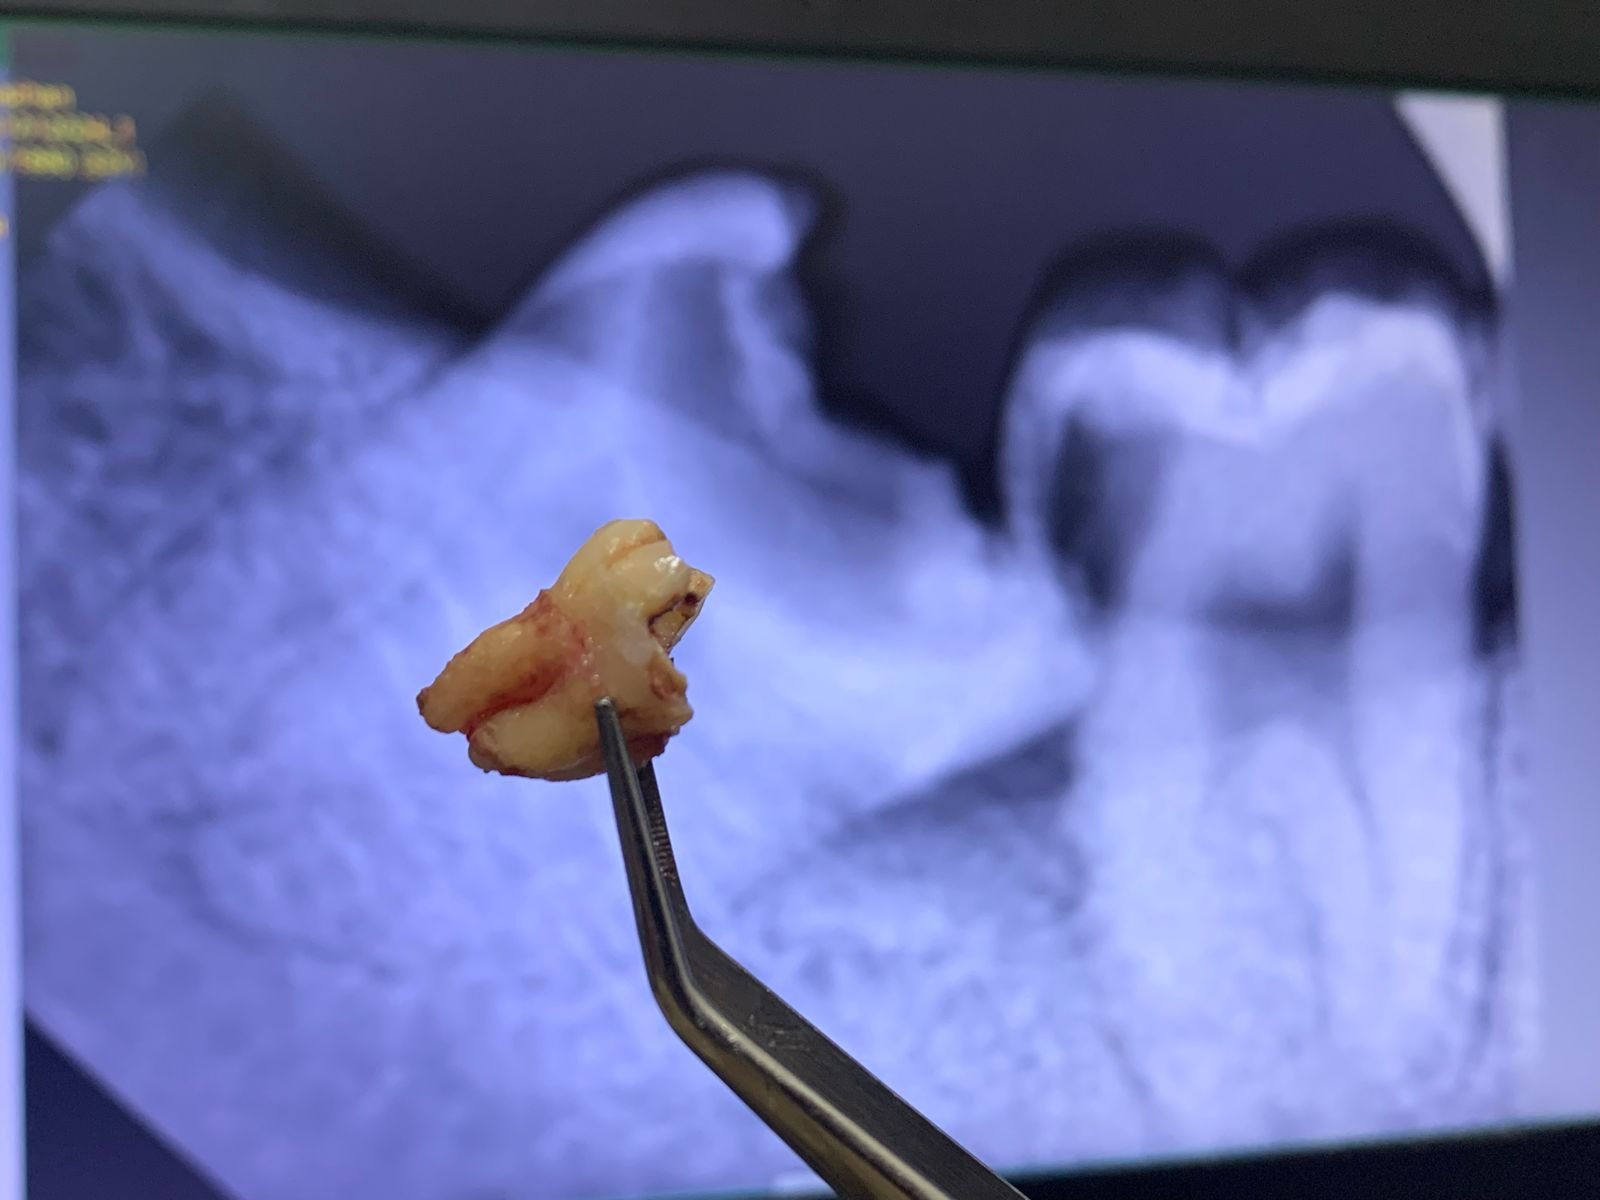

Kasus paling sering yang membutuhkan odontektomi terjadi pada gigi bungsu (molar tiga). Gigi bungsu yang tumbuh miring atau kekurangan ruang di rahang sering menimbulkan nyeri, infeksi, serta gangguan pada gigi sebelahnya.

ciri ciri impaksi gigi dan perlu operasi gigi bungsu

Kapan Odontektomi Dibutuhkan?

Pasien biasanya membutuhkan odontektomi dalam kondisi berikut:

• Gigi bungsu impaksi, tumbuh tidak sempurna dan menekan gigi di sebelahnya.

• Infeksi gusi berulang (perikoronitis) karena gigi hanya muncul sebagian.

• Kerusakan gigi sebelahnya akibat dorongan dari gigi bungsu.

• Kista atau tumor rahang yang berkembang di sekitar gigi bungsu.

• Rencana ortodonti (behel) yang mengharuskan dokter menciptakan ruang tambahan pada rahang.